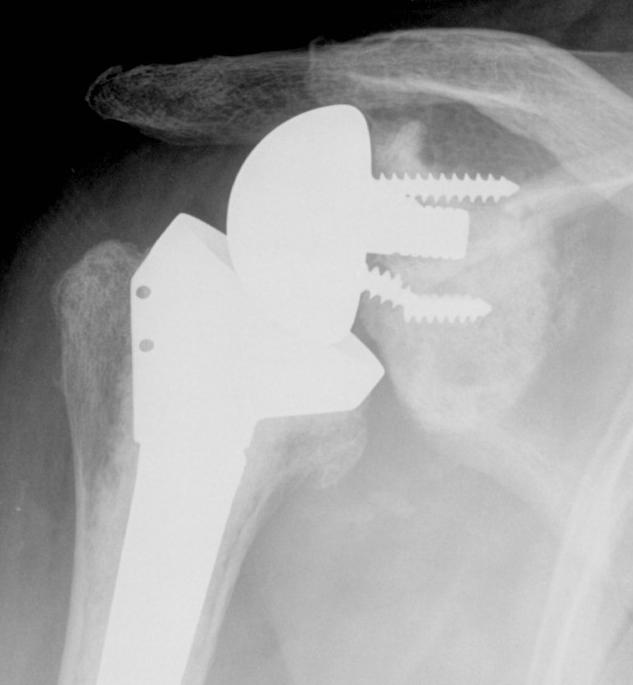

Reverse TSR Loose Glenosphere from Metaglene

Glenosphere loosening from metaglene